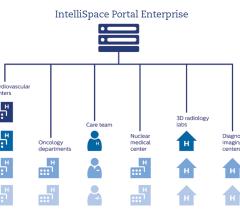

Physicians are struggling with too much of a good thing. They have never had so much information about their patients. But the data are scattered across multiple departments and across the enterprise. Finding relevant information can be like finding a needle in a haystack. Enterprise imaging is evolving to address the problem — to find and assemble relevant information so that accurate diagnoses can be made efficiently and effectively.

At the 2018 HIMSS Annual Conference & Exhibition, Siemens Healthineers showcased new additions and updates to its Digital Ecosystem, an open and secured environment for healthcare stakeholders that houses a range of digital offerings from Siemens Healthineers and other partners based on shared healthcare data. Within the Siemens Healthineers cloud, different data sources can be integrated and processed, supporting a large variety of application types.